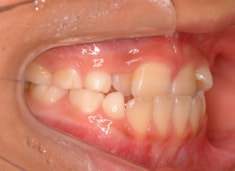

骨年齢は実年齢よりも低めなので、今後下顎の旺盛な成長が見込まれます。

検査時のレントゲン分析では、上下顎の関係は、上顎の劣成長があり下顎前突傾向という値がでておりましたが、前歯ジャンプ後はフェイスマスクの効果もあり、上下顎の関係は正常化しています。

上顎が若干優位になっていますので、今後の下顎の成長のための貯金になっているくらいです。